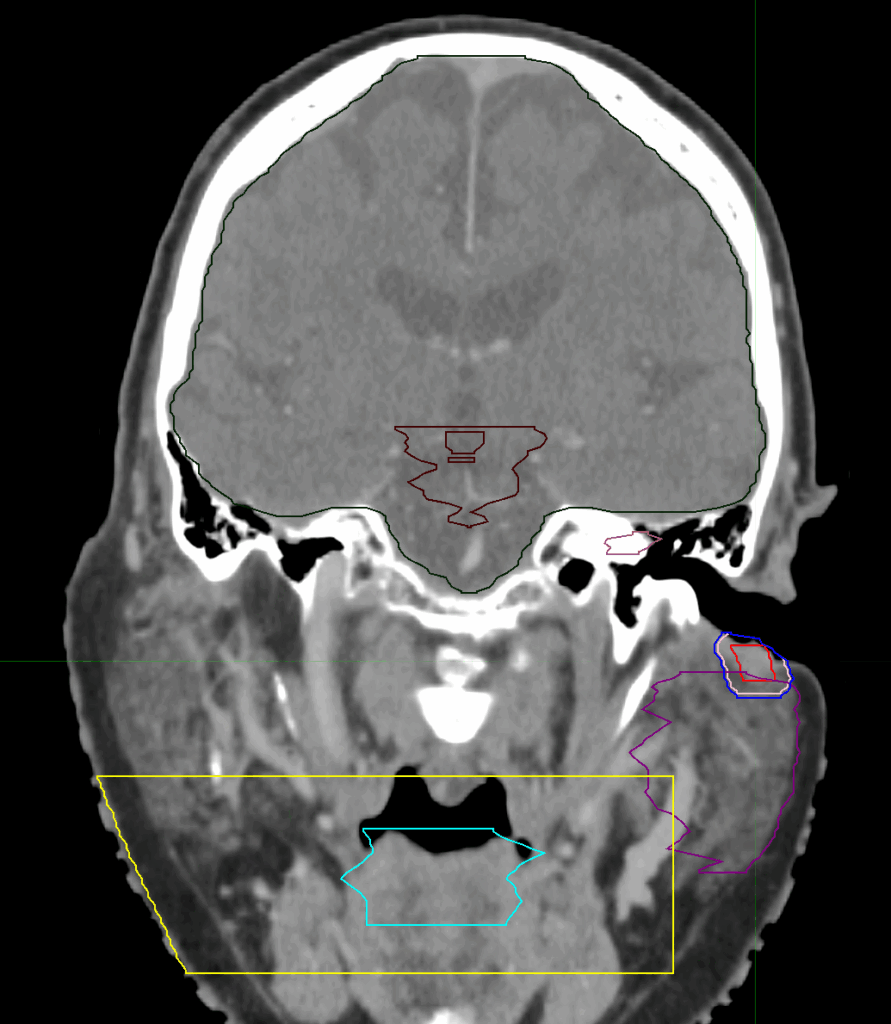

Planning CT Images